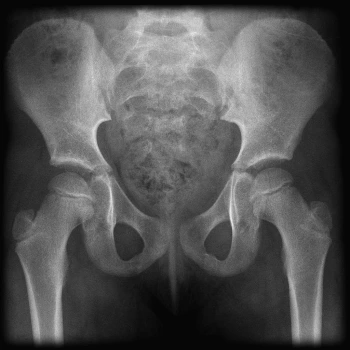

hip.jpeg 정상 고관절 사진, 일과성 고관절 활액막염은 단순 방사선 촬영 검사에서는 이상 소견이 관찰되지 않는다.